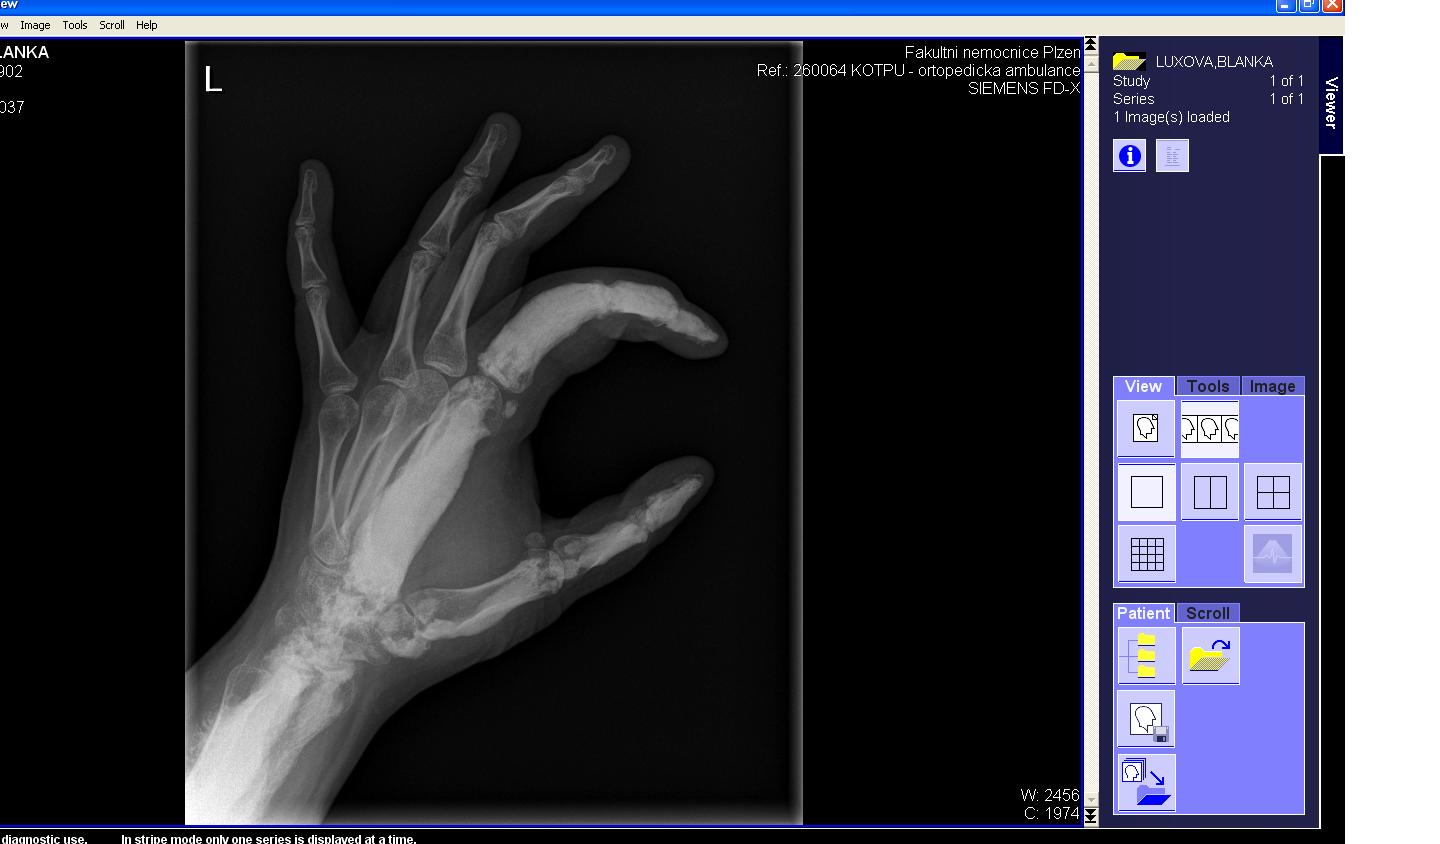

Area(s) affected:  Left arm and hand

Hi.  I am Blanka from Czech Republic. I had Melo since 10 years old, now I am 26, have one 5 years old healthy daughter, but still live in pain.

I am sending you some photos from RTG and CT and scinti scam from last month.